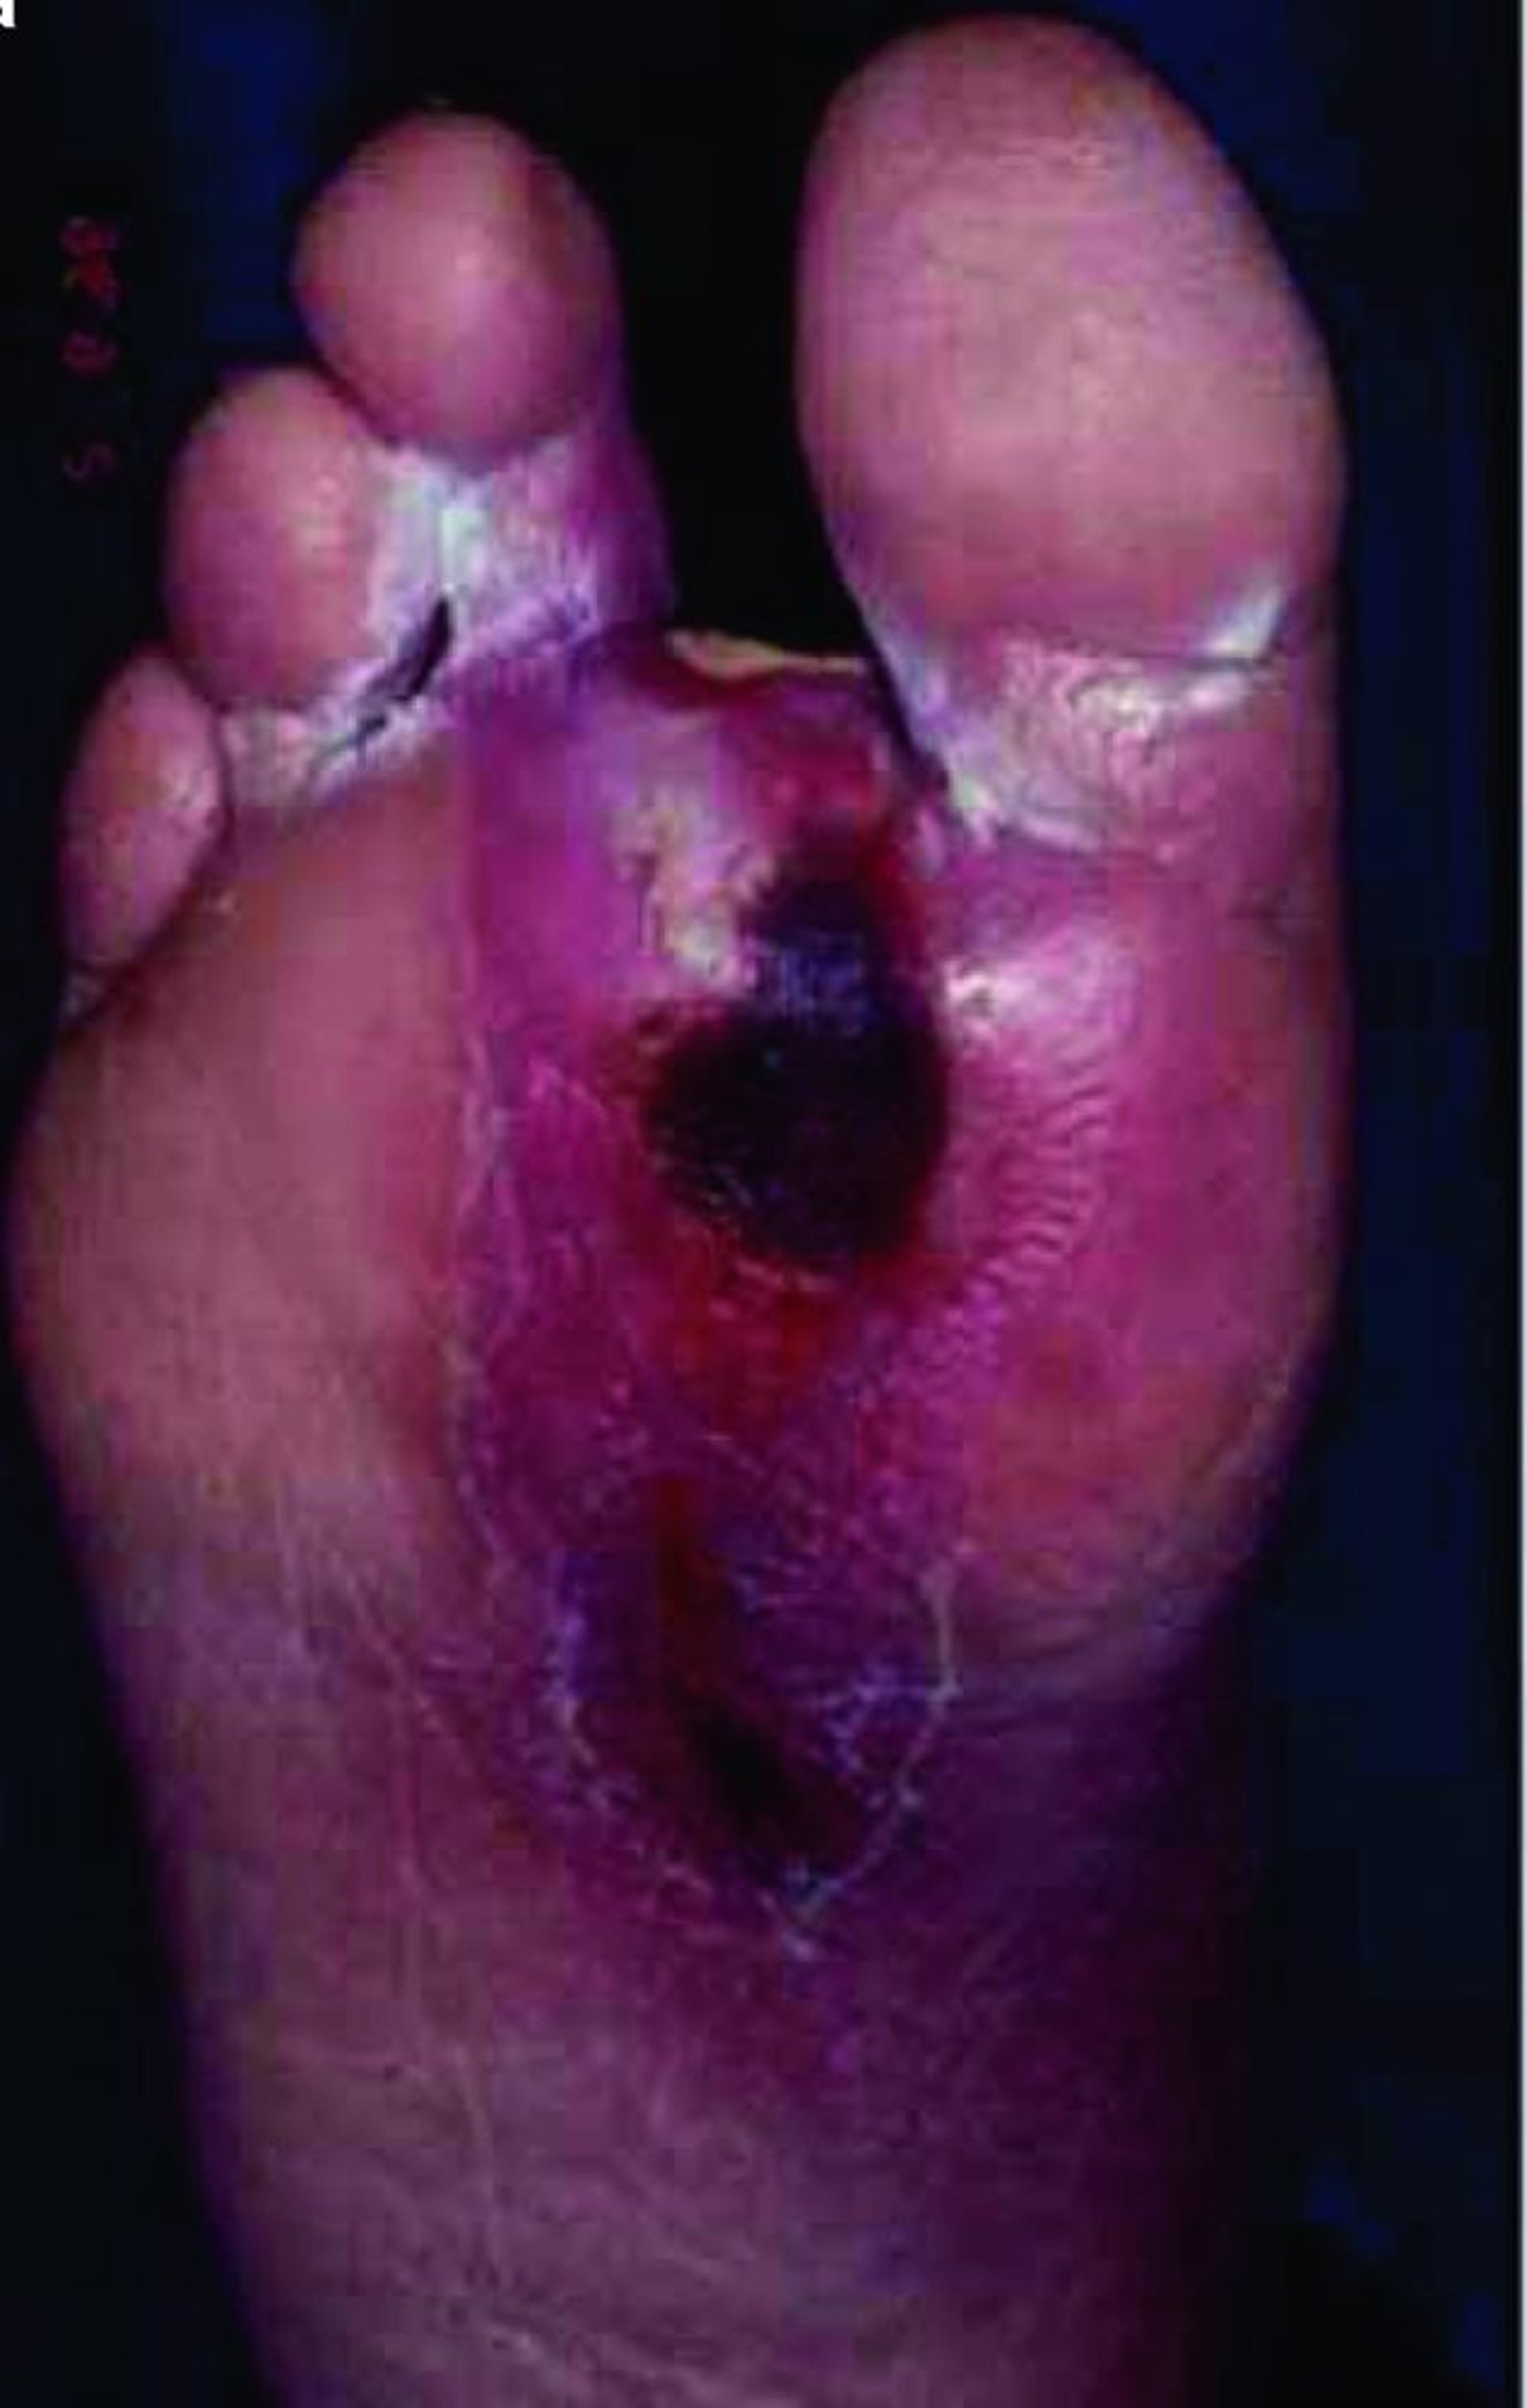

Úlcera do pé

Um paciente com diabetes frequentemente desenvolve doença microvascular, que pode prejudicar a cicatrização da pele; assim, mesmo pequenas rupturas na integridade da pele podem evoluir para úlceras profundas e se infectar facilmente, sobretudo nos membros inferiores.